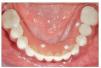

En el plazo de 48 h después de la cirugía, se colocaba una prótesis provisional de resina acrílica con 10 dientes (fig. 3). Los contactos en céntrica y laterales se limitaban a la zona intercanina. Se tomaba una radiografía panorámica para comprobar la posición de los implantes y su acoplamiento con los componentes de la prótesis.

Figura 3. Prótesis provisional colocada a las 3 h de la cirugía.